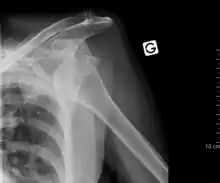

Anterior dislocation of the left shoulder.

A shoulder dislocation often occurs as a result of a fall onto an outstretched arm or onto the shoulder.[3] Diagnosis is typically based on symptoms and confirmed by X-rays.[2] They are classified as anterior, posterior, inferior, and superior with most being anterior.[2][1]

There are three main types of dislocations: anterior, posterior, and inferior.

Anterior (forward)

X-ray at left shows anterior dislocation in a young man. X-ray at right shows the same shoulder after reduction and internal rotation, revealing a Bankart lesion and a Hill-Sachs lesion.

In over 95% of shoulder dislocations, the humerus is displaced anteriorly.[6] In most of those, the head of the humerus comes to rest under the coracoid process, referred to as sub-coracoid dislocation. Sub-glenoid, subclavicular, and, very rarely, intrathoracic or retroperitoneal dislocations may also occur.[7]

Anterior dislocations are usually caused by a direct blow to, or fall on, an outstretched arm. The person typically holds his/her arm externally rotated and slightly abducted.